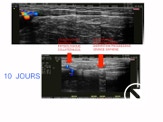

Sous l’effet de la radiofréquence ou du laser , il se rétracte  , s’oblitère et se résorbe progressivement .

A 10 jours , le processus est déjà visible . A 3 mois , il persiste un cordon fibreux qui va disparaitre en 1 an environ .